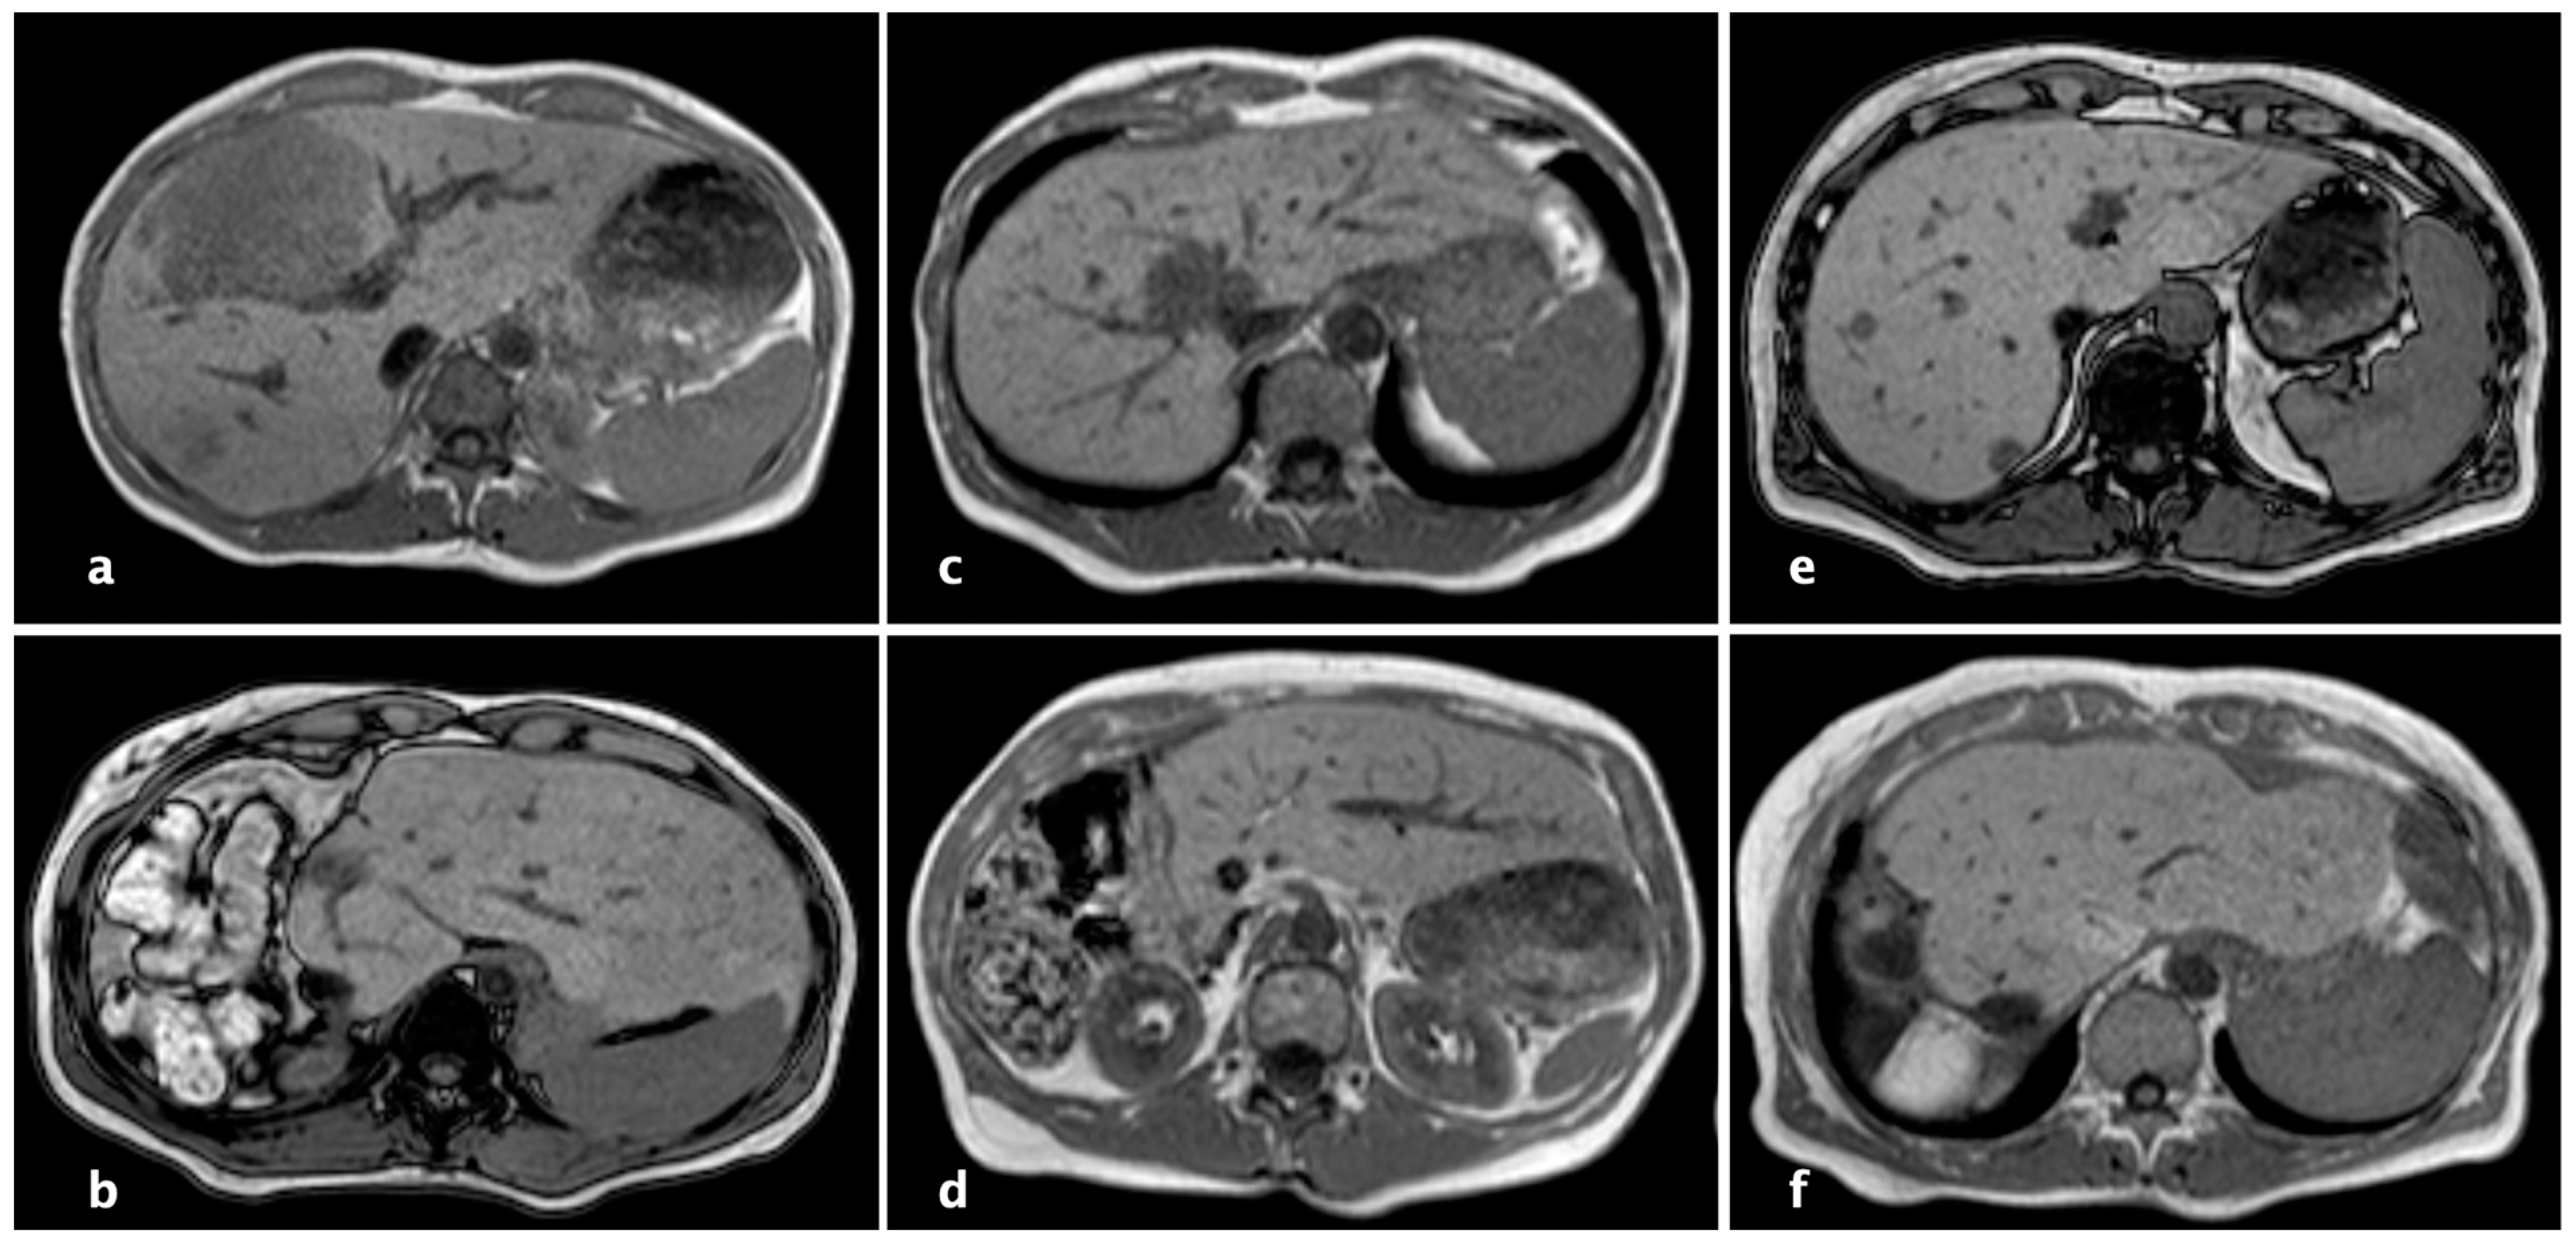

2.3. Technique of rALPPS

- Perrakis, A.; Rahimli, M.; Gumbs, A.A.; Negrini, V.; Andric, M.; Stockheim, J.; Wex, C.; Lorenz, E.; Arend, J.; Franz, M.; et al. Three-Device (3D) Technique for Liver Parenchyma Dissection in Robotic Liver Surgery. J. Clin. Med. 2021, 10, 5265. [Google Scholar] [CrossRef] [PubMed]